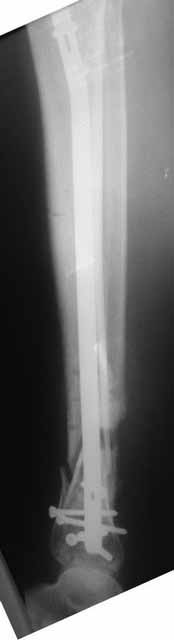

Примерная ситуация. Пациент 37 лет. Синтезировали где-то пластинкой. Попал к нам через 2 месяца.

19 апреля убрали через проколы пластину с винтами, пересекли fibula, наложили аппарат.

Немного потянули по оси, убрали вальгус, ротацию. 22 апреля (на 3-е сутки) заштифтовали окончательно. 29 апреля выписали из отделения. На все ушло 10 дней.